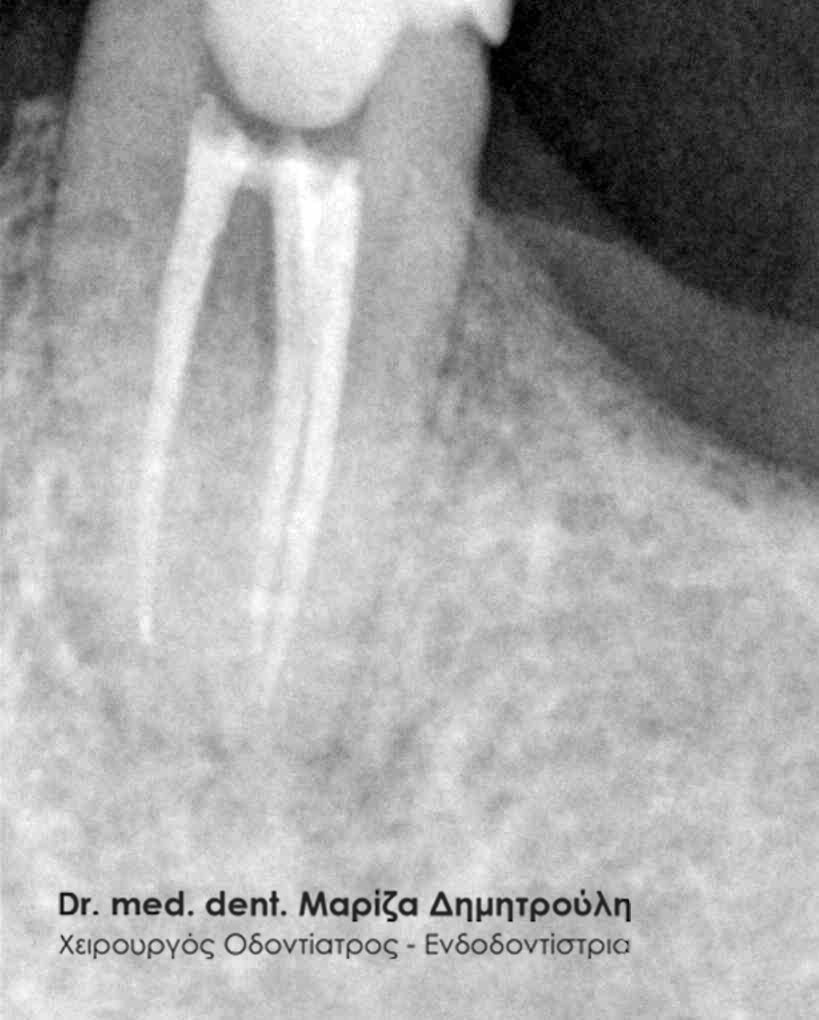

Με την απονεύρωση ο ενδοδοντολόγος αφαιρεί το νεκρό ή μολυσμένο πολφό, όπως και τα νεύρα του δοντιού. Αφού επεξεργαστεί και καθαρίσει πλήρως το δόντι σε 2 ή 3 συνεδρίες,ανάλογα με το βαθμό δυσκολίας του δοντιού, στη συνέχεια εμφράσσονται οι ριζικοί σωλήνες με ένα ειδικό υλικό που λέγεται γουταπέρκα. Σκοπός της έμφραξης των ριζικών σωλήνων είναι η αποφυγή επαναμόλυνσης του πολφού. Στη συνέχεια ακολουθεί η αποκατάσταση του δοντιού με σφράγισμα ή στεφάνη ανάλογα με το έκταση της οδοντικής βλάβης.

Στην περίπτωση αυτή ο ασθενής παραπέμπεται συνήθως στον ενδοδοντολόγο, με σκοπό να ξεκινήσει την επανάληψη της απονεύρωσης. Αυτό σημαίνει ότι ο ενδοδοντιστής θα αφαιρέσει μέσα από τις ρίζες του δοντιού την “παλιά απονεύρωση” ( δηλαδή το υλικό με το οποίο είχαν “γεμίσει” παλιά οι ριζικοί σωλήνες του δοντιού ), θα επεξεργαστεί και θα καθαρίσει εκ νέου τους ριζικούς σωλήνες του δοντιού. Εφόσον το δόντι παραμένει ασυμπτωματικό, η θεραπεία θα ολοκληρωθεί με την έμφραξη τόσο των ριζικών σωλήνων ( με γουταπέρκα, δηλαδή το υλικό με το οποίο εμφράσσονται οι ρίζες των δοντιών κατά την απονεύρωση ) όσο και της μύλης του δοντιού ( με λευκό σφράγισμα ).

Πρίν

Μετά